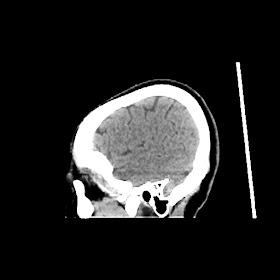

A 50 years old woman with headache, back pain, ghabrahat